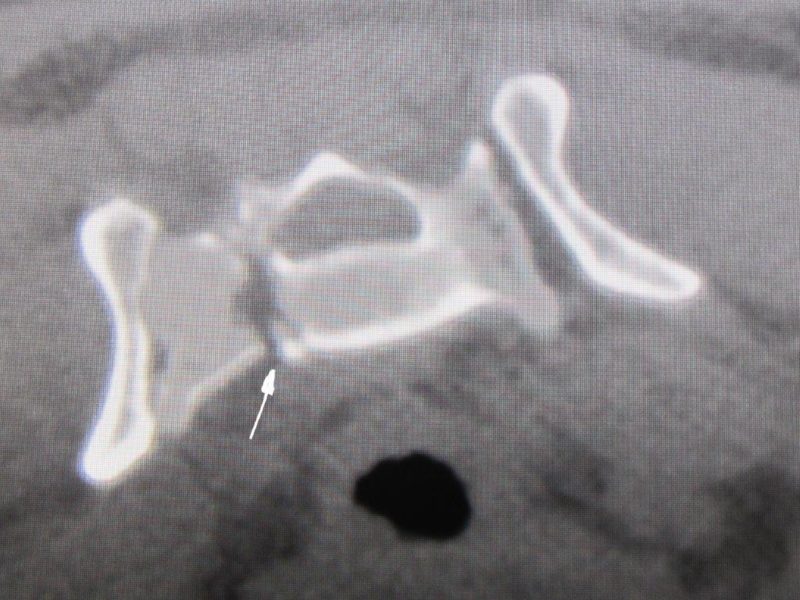

Wie auf dem Bild 3 dargestellt, zeigt sich am hinteren Rand des Acetabulum (Gelenkpfanne) ein kleines Knochenstück, das nur dezent verschoben ist. Die Gelenkpfanne ist im gesamten vorderen Teil der Gelenkfläche intakt.

Auf der Abbildung (Bild 4 mit Pfeil) lässt sich eine Fraktur (Bruch) des Kreuzbeins mit einer geringgradigen Verschiebung darstellen. Diese verläuft in der Längsachse des Knochens und tangiert nur ganz gering den Rückenmarkskanal, in dem das Rückenmark und die Nerven verlaufen. Zusammen mit den Besitzern entschlossen wir uns, vorerst auf eine Operation zu verzichten und das Tier nur in einer Box ruhig zu halten, sowie die notwendigen Medikamente zu geben. Es sollte genauestens darauf geachtet werden, daß die normalen Körperfunktionen mit Urin- und Kotabsatz funktionierten und keine nervalen Ausfälle aufträten.